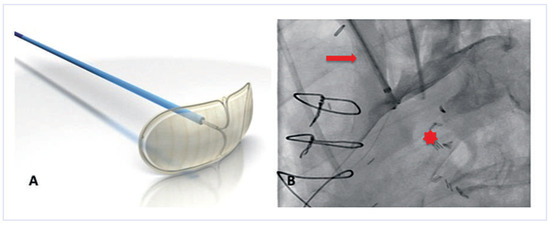

An 83-year-old man with ischaemic heart disease and a triple bypass in 2007 presented to the emergency department with increasing shortness of breath and weight gain of 5 kg over one month [...]